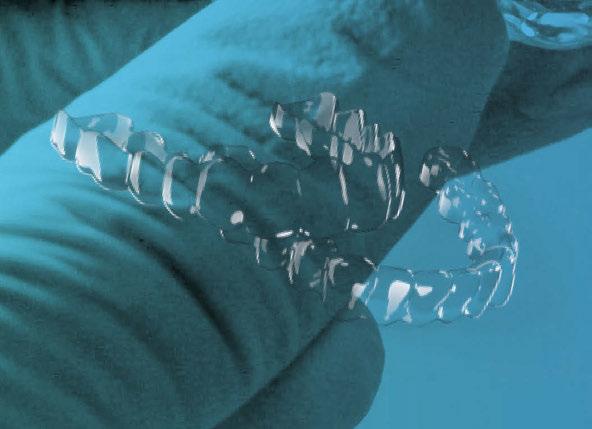

Te enseñamos cómo confeccionar una férula quirúrgica digital y un ClinCheck o Approver de cirugía ortognática. Aprenderás sobre protocolo y planificación y te daremos consejos y soluciones para quepuedas abordar incluso los casos más complejos.

POLA FOR ALIGNERS

Con férula